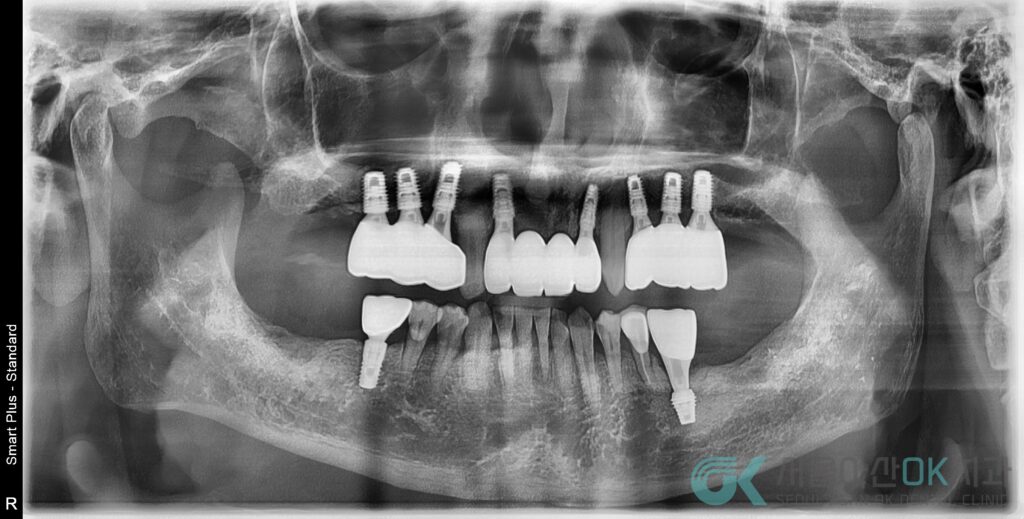

- 보철 단계

- 보철물을 제작을 주문하는 날, 전악 파노라마 + 부분 스케일링으로 잇몸 상태 재평가하였습니다.

- 그 후 #36 커스텀 어버트먼트 + 지르코니아 크라운 최종 장착하였는데요.

- SCRP 방식, 30Ncm로 나사 조임

- 파노라마 및 치근단 촬영 → 보철물 경계 불량, 나중엔 스크류 파절까지 확인

- 기존 크라운을 제거하고, 파절된 스크류 조각을 flap을 열어 BUR로 제거

- 임플란트 자체는 유지 가능한 상태로 판단하여

- 새로 스캔 바디 인상

- 덴티스 시스템에 맞는 커스텀 어버트먼트 + 지르코니아 크라운 재제작

- 최종 보철 장착 및 SCRP 홀 레진 충전까지 완료